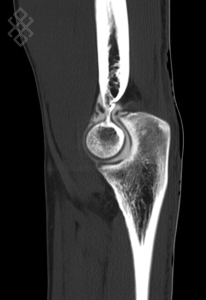

Arthroscanner du Coude

La durée de l'examen est d'environ 20 minutes. Pour repérer la zone souahitée, le radiologue fera une scopie. Ensuite, il effectuera une désinfection puis une anesthésie locale. Pour l'injection du produit de contraste iodé, il introduira une aiguille dans la zone repérée, puis il appliquera un pansement étanche. Enfin, vous serez installés afin d'effectuer le scanner du coude.